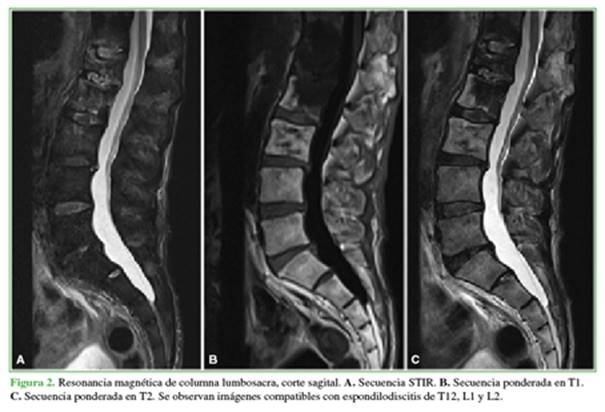

Ante las comorbilidades del paciente, la ausencia de un diagnóstico de certeza y la mala evolución, se indicó una endoscopia con fines diagnóstico y terapéutico. El procedimiento se efectuó bajo sedación anestésica, con un abordaje posterolateral izquierdo uniportal a 10 cm de la línea media a nivel de L1-L2 (Figura 3).